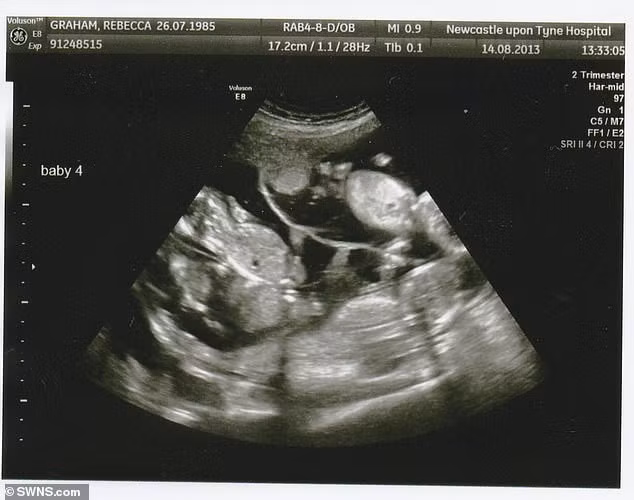

Trở lại câu chuyện mang thai tư, Becky cho biết, cô phát hiện mình có bầu 4 bé khi siêu âm tuần thứ 12 tại một bệnh viện ở Carlisle. "Một cơn chấn động thực sự", cô nhớ lại.

"Hàng triệu suy nghĩ lướt qua tâm trí chúng tôi. Làm thế nào có thể xoay xở với cả 4 đứa trẻ cùng lúc đây? Chúng tôi lúc nào cũng cố gắng phải giữ bằng được cả 4 bé. Thật là một thai kỳ đáng sợ bởi những rủi ro tiềm ẩn. Tuy nhiên, chúng tôi cảm thấy vô cùng may mắn vì đã thụ thai tự nhiên được 4 bé".

Chị Becky Graham chỉ phát hiện ra mình đang mang thai bốn ở tuần thứ 12 qua bức ảnh siêu âm. Mặc dù bị sốc, cô vẫn quyết định: "Chúng tôi sẽ giữ cả 4 đứa trẻ lại".

Do tính chất phức tạp của thai kỳ, Becky Graham được chuyển tới một bệnh viện ở Newcastle, nơi cô vào khám thai 2 lần/tuần.